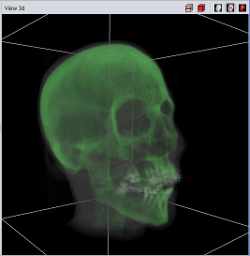

|

|

|

| Point Cloud | Marching Cube | Texture |

Currently four different segment visualization methods can be choosen.

The 3D segment visualization methods can be set for each individual segment. This can be done in the "view 3d" tool pane.